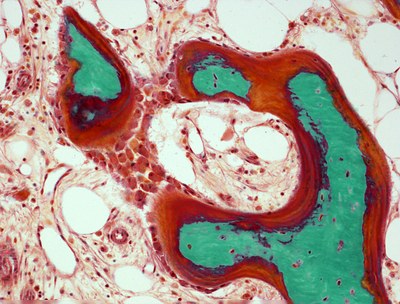

JPRoux2